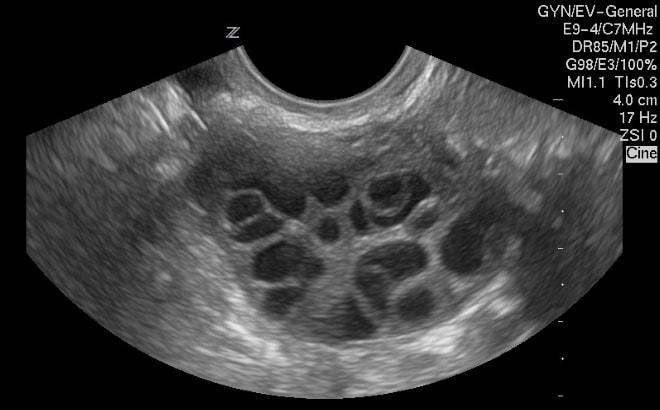

При мультифолликулярных яичниках (МФЯ) и поликистозных яичниках на ультразвуковом исследовании можно увидеть множество образований на этих органах. В случае МФЯ это не всегда указывает на наличие заболевания. МФЯ представляет собой множество зрелых фолликулов, готовых к овуляции. Если они разрываются одновременно, это может привести к многоплодной беременности. Мультифолликулярные яичники считаются нормальной индивидуальной особенностью организма и, в отличие от поликистоза, не требуют лечения. Лечение назначается только в случае появления кист или при нарушении гормональной функции эндокринной системы.

Эксперты в области гинекологии отмечают, что мультифолликулярные и поликистозные яичники имеют как сходства, так и различия, которые важно учитывать при диагностике и лечении. Оба состояния характеризуются наличием множества фолликулов, однако в случае поликистозных яичников наблюдается также увеличение их размера и наличие кист, что может приводить к гормональным нарушениям. Мультифолликулярные яичники, как правило, не сопровождаются такими серьезными изменениями, и их функционирование может оставаться в пределах нормы. Эксперты подчеркивают, что правильная диагностика этих состояний требует комплексного подхода, включая ультразвуковое исследование и анализ гормонального фона. Понимание различий между этими состояниями помогает в выборе оптимальной стратегии лечения и улучшении качества жизни пациенток.

При проведении гинекологического ультразвукового исследования можно легко перепутать данные симптомы. Поэтому для их точного различия необходимо проводить лабораторные анализы крови и фолликулометрию.

- визуальные характеристики на ультразвуке;